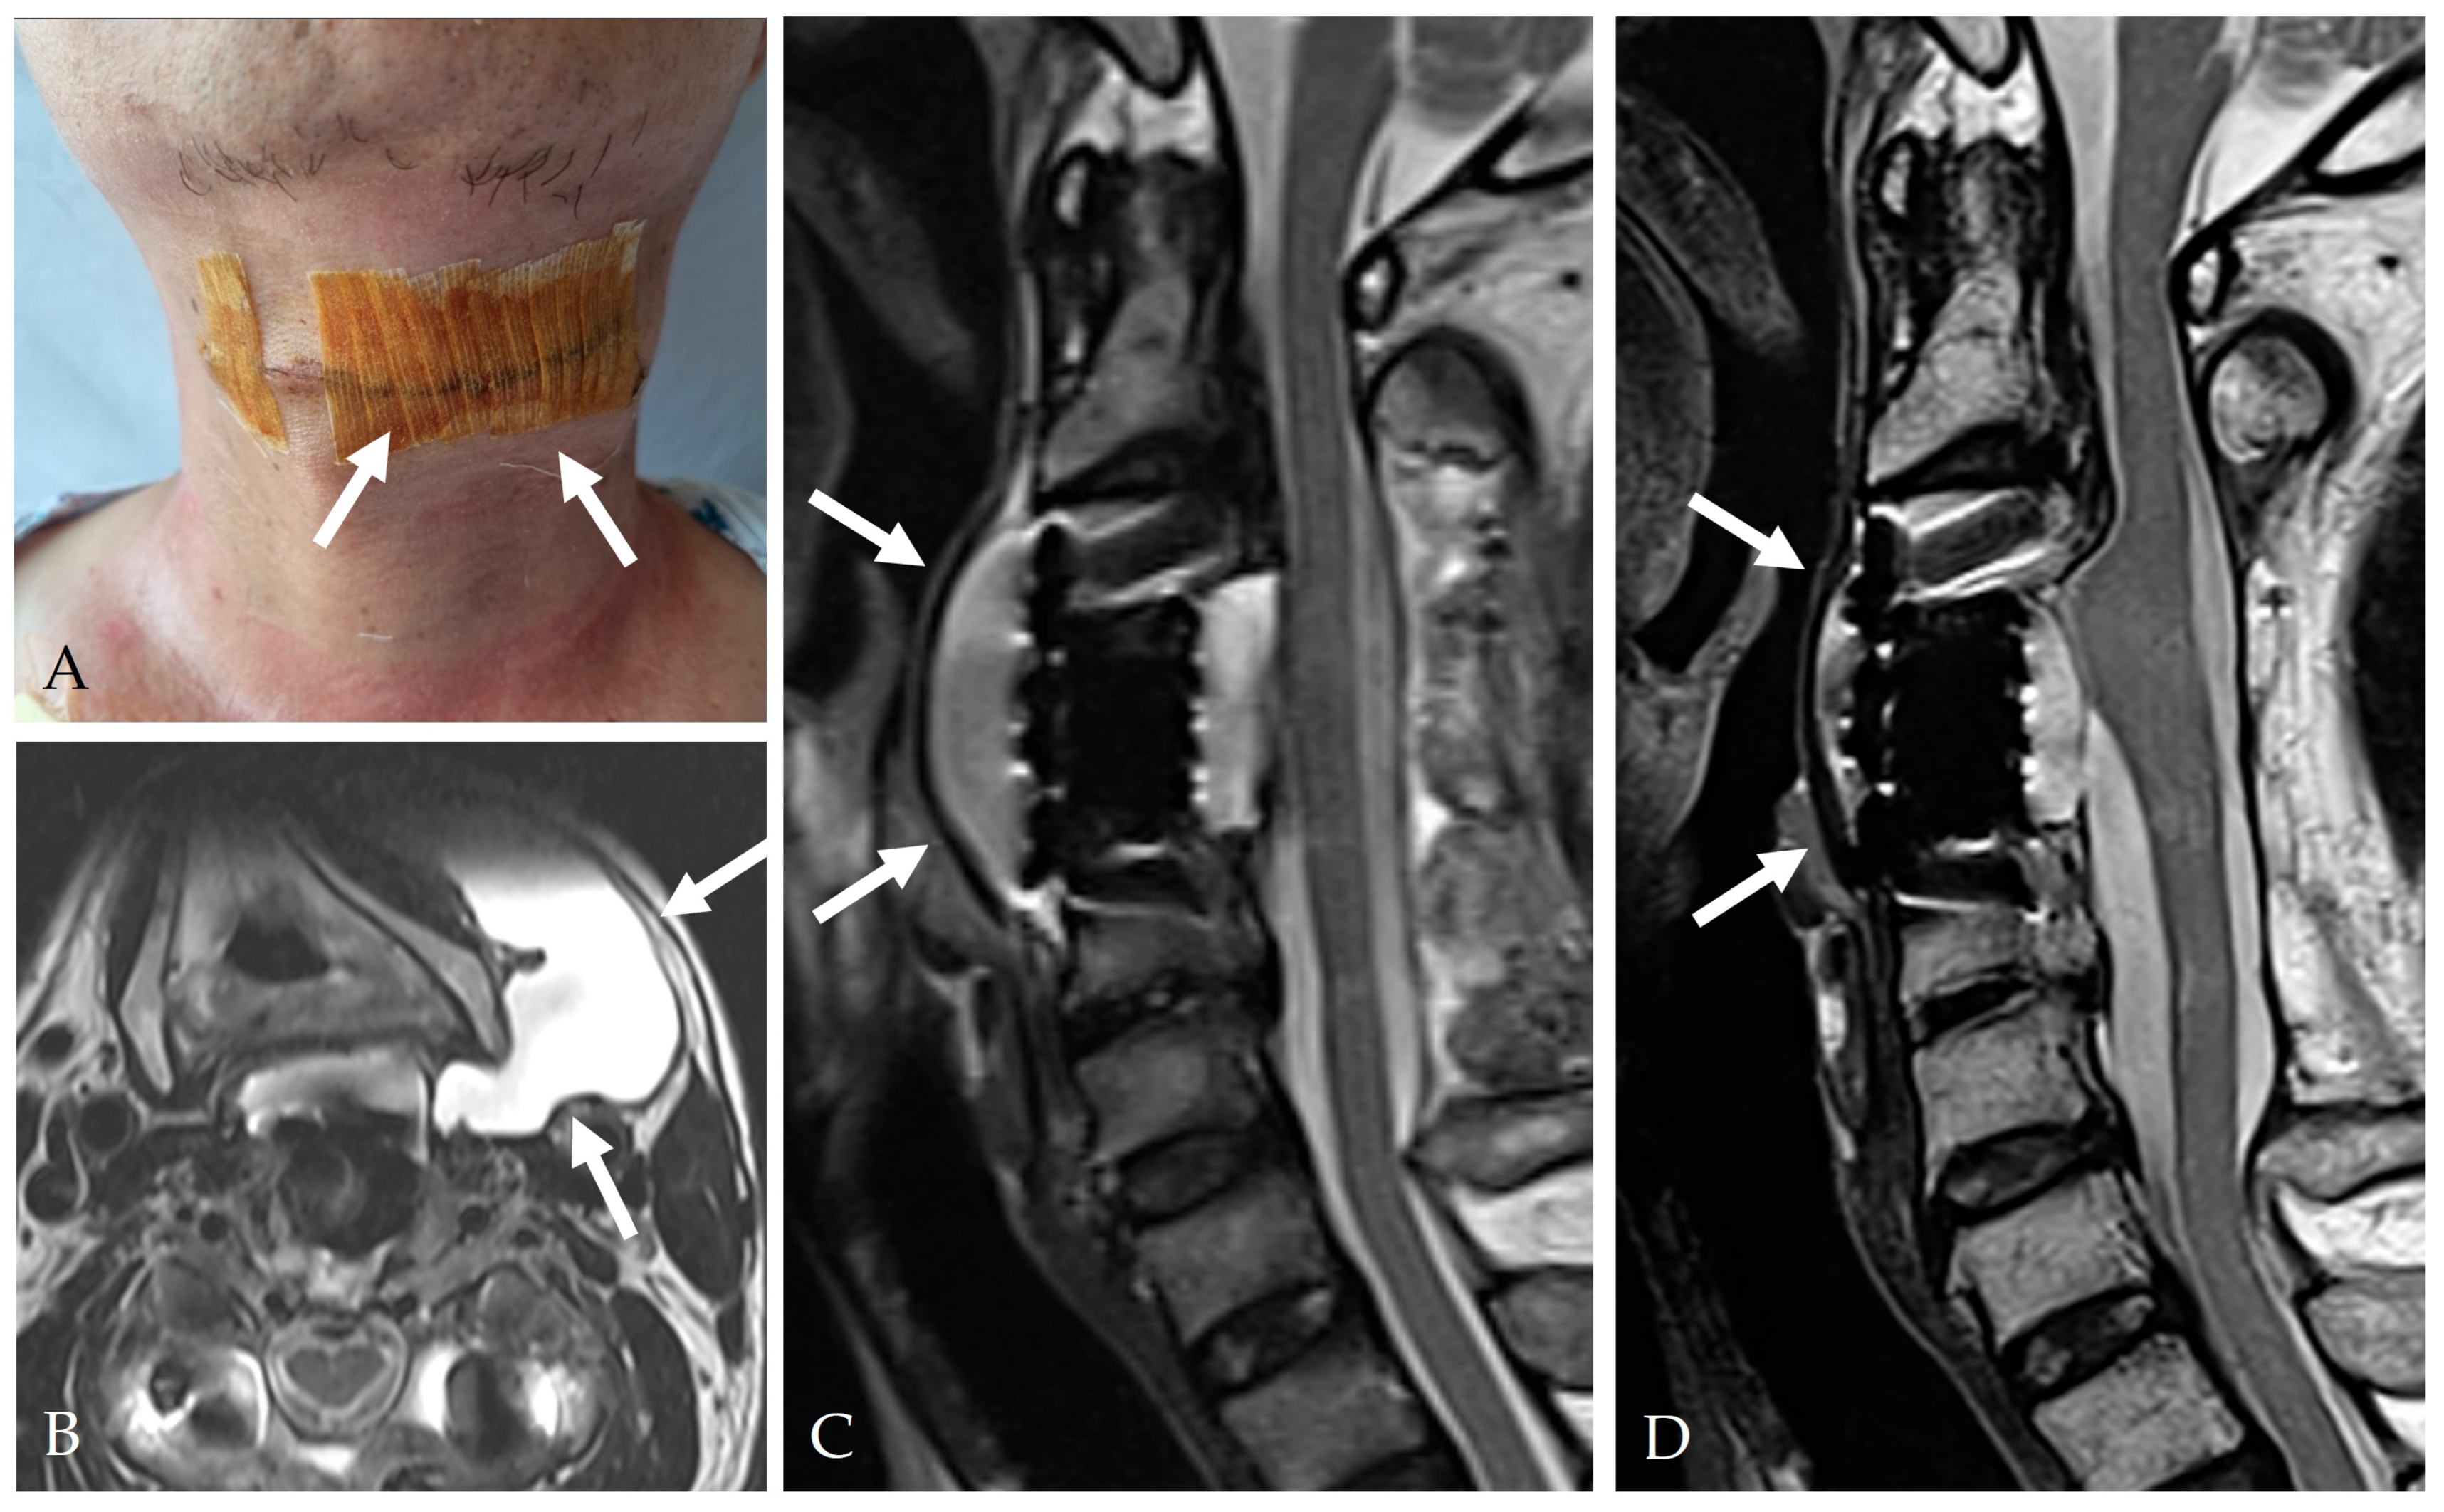

5.4. Pseudomeningocele Management

- <2 cm → observation

- 2–4 cm → aspiration and compression

6.5. Pseudomeningocele and Late Recurrence

- Lien, J.R.; Patel, R.D.; Graziano, G.P. Sternocleidomastoid muscular flap for persistent CSF leak after anterior cervical spine surgery. J. Spinal Disord. Tech. 2013, 26, 449–453. [Google Scholar] [CrossRef]

- Andrew, S.A.; Sidhu, K.S. Cervical-peritoneal shunt placement for postoperative cervical pseudomeningocele. J. Spinal Disord. Tech. 2005, 18, 290–292. [Google Scholar] [PubMed]

- Hyun, S.J.; Rhim, S.C.; Ra, Y.S. Repair of a cerebrospinal fluid fistula using a muscle pedicle flap: Technical case report. Neurosurgery 2009, 65, E1214–E1215. [Google Scholar] [CrossRef] [PubMed]